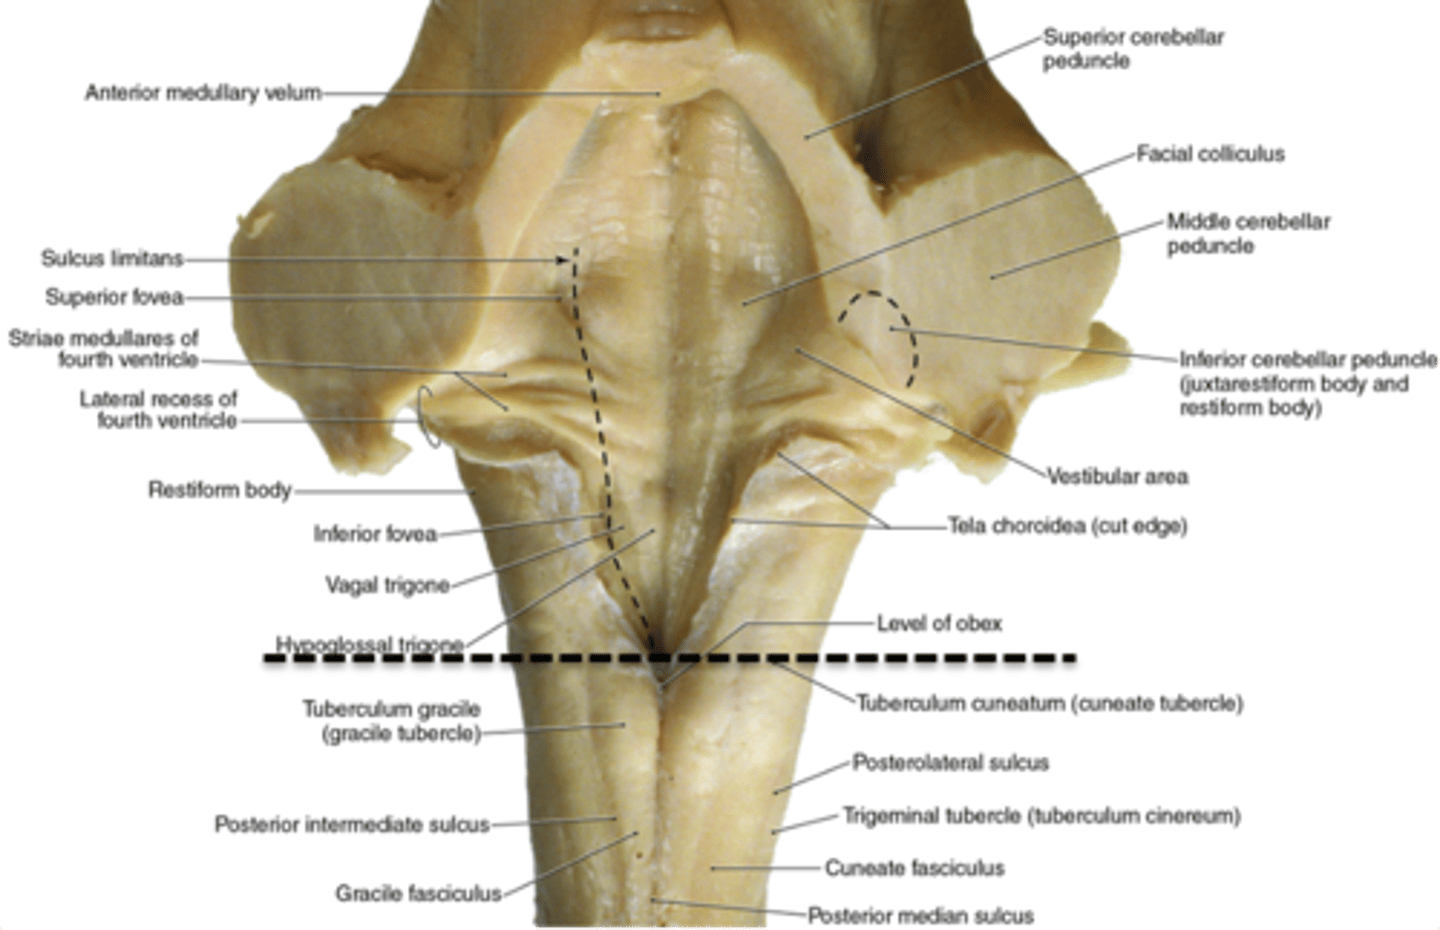

what are the 2 tubercles found on the closed (caudal) medulla?

1. gracile tubercles (more medial, touch/proprioception from lower body)

2. cuneate tubercles (more lateral, touch/proprioception from upper body)